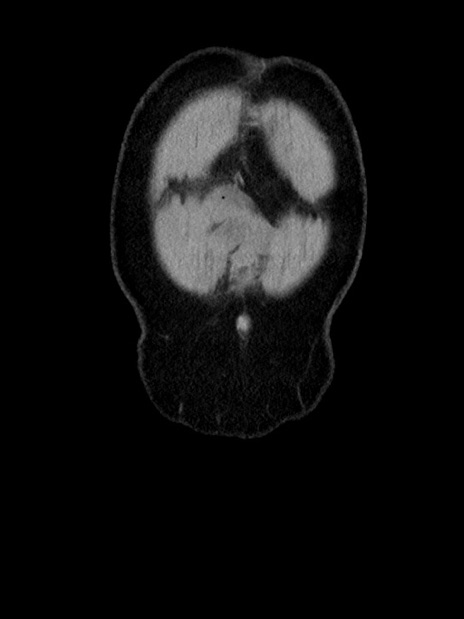

横断像